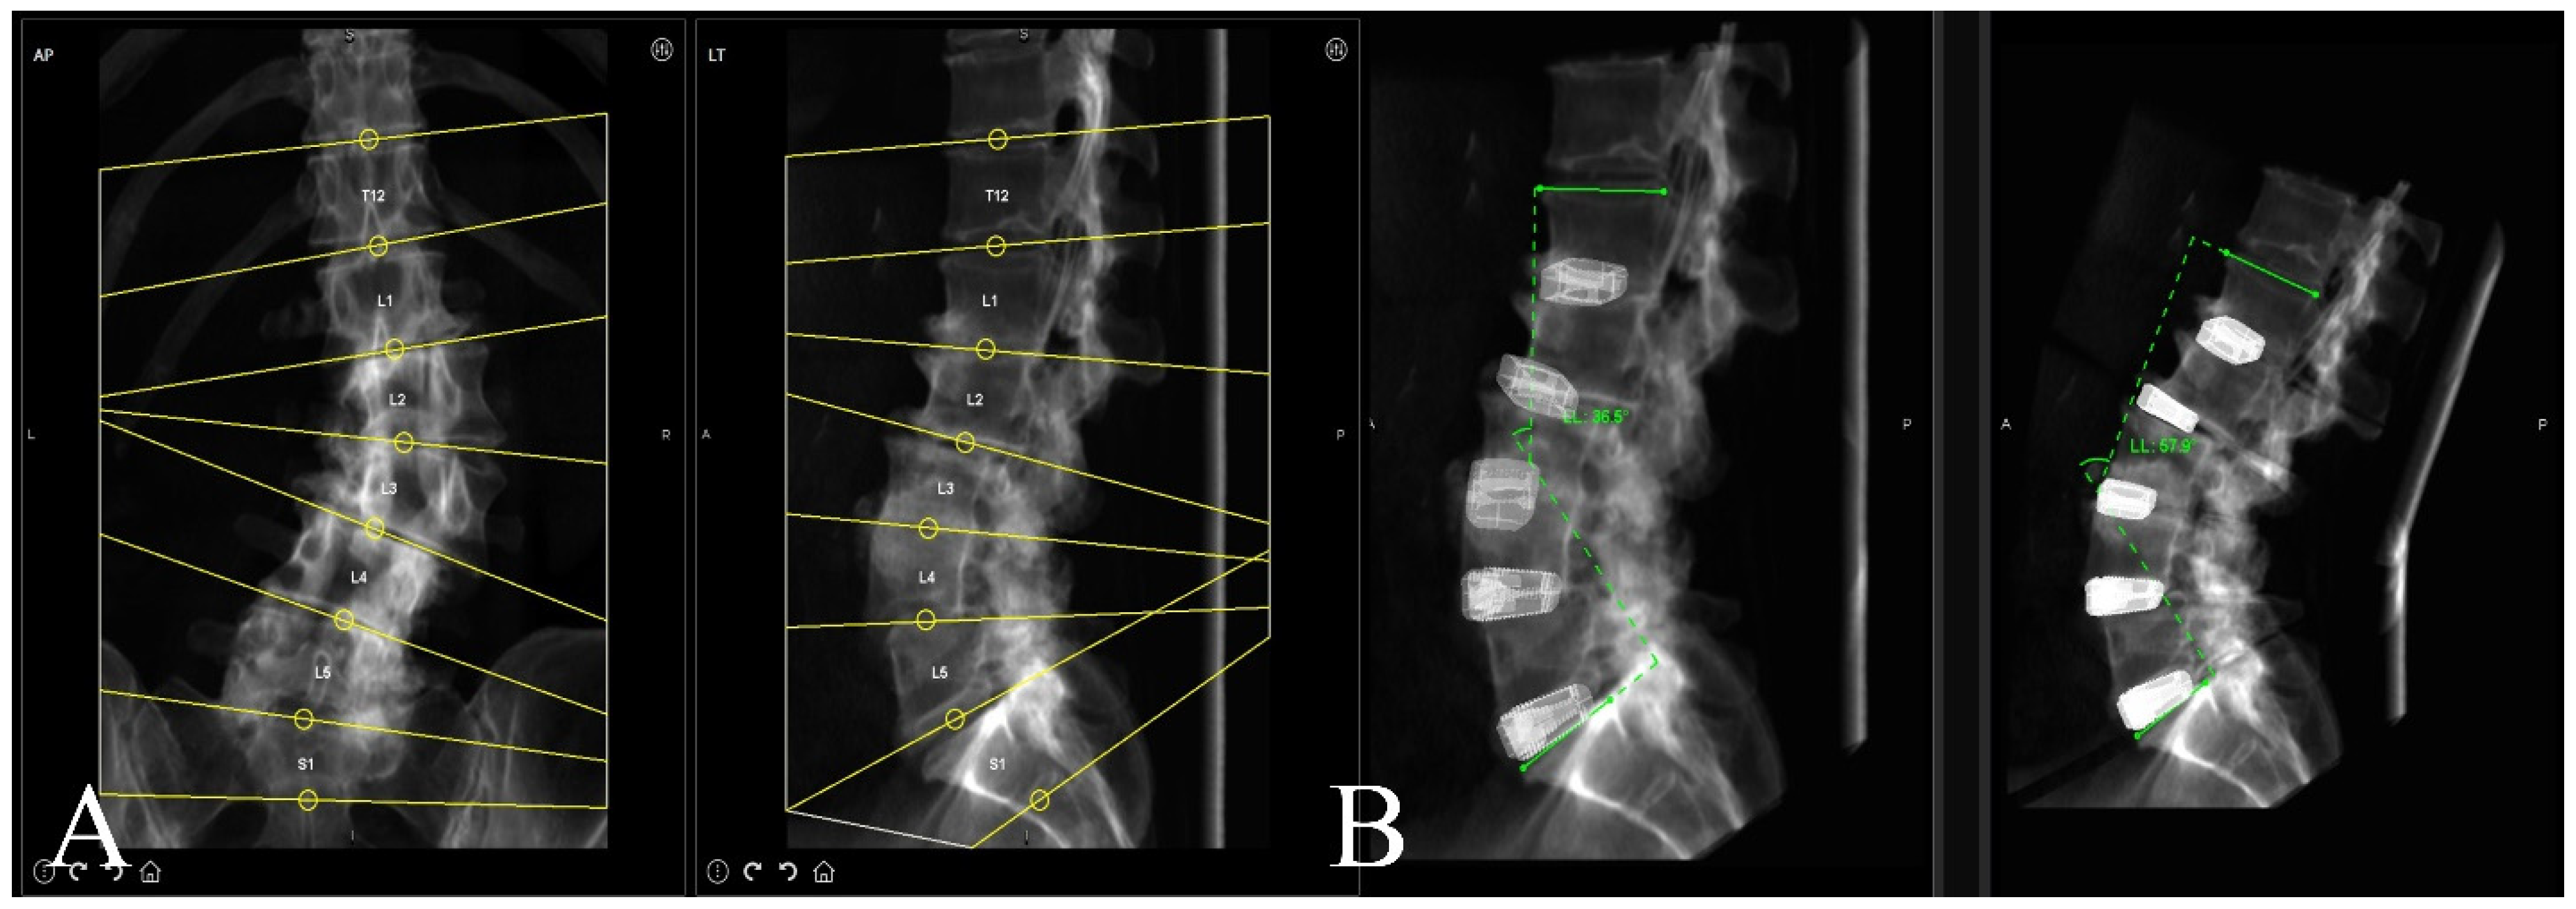

A preoperative thin-cut CT scan is obtained and loaded into the planning software associated with the spinal robotics system (Mazor X Robotics Planning Software Version 5.0 with X-Align, Medtronic Sofamor Danek, Minneapolis, MN, USA) (Figure 1A). Interbody cages are then planned and simulated. Of note, the software assumes full movement of the chosen segment based on cage geometry and marked endplate surfaces, and under-correction of the simulation may oftentimes be needed due to rigid deformities or facet ankylosis and hypertrophy (Figure 1B and Figure 2). With this correction provided, pedicle and iliac screws are then planned from the UIV to S2 and bilateral rods are simulated after each screw to confirm appropriate planar alignment (Figure 3). Adjustments to the trajectories of the pedicle screws can be made to ensure easy subfascial passage. Satellite accessory rods are planned using lateral-to-medial screw trajectories with positions outside of the main rod. While open surgical techniques allow for satellite rod placement with dual-headed screws or rod–rod domino connectors, the lack of direct visualization in MIS makes these strategies prohibitive and therefore satellite rods are usually not able to be directly connected to the main rod (Figure 4).

Figure 1. (A) Robotic software automatic segmentation of each vertebral level as a separate independent volume to allow for both screw fixation and interbody implant planning. (B) Sagittal simulation of interbody cage placement with movement of each individual vertebral segment to assess if appropriate sagittal correction can be achieved with minimally invasive placement of interbodies.